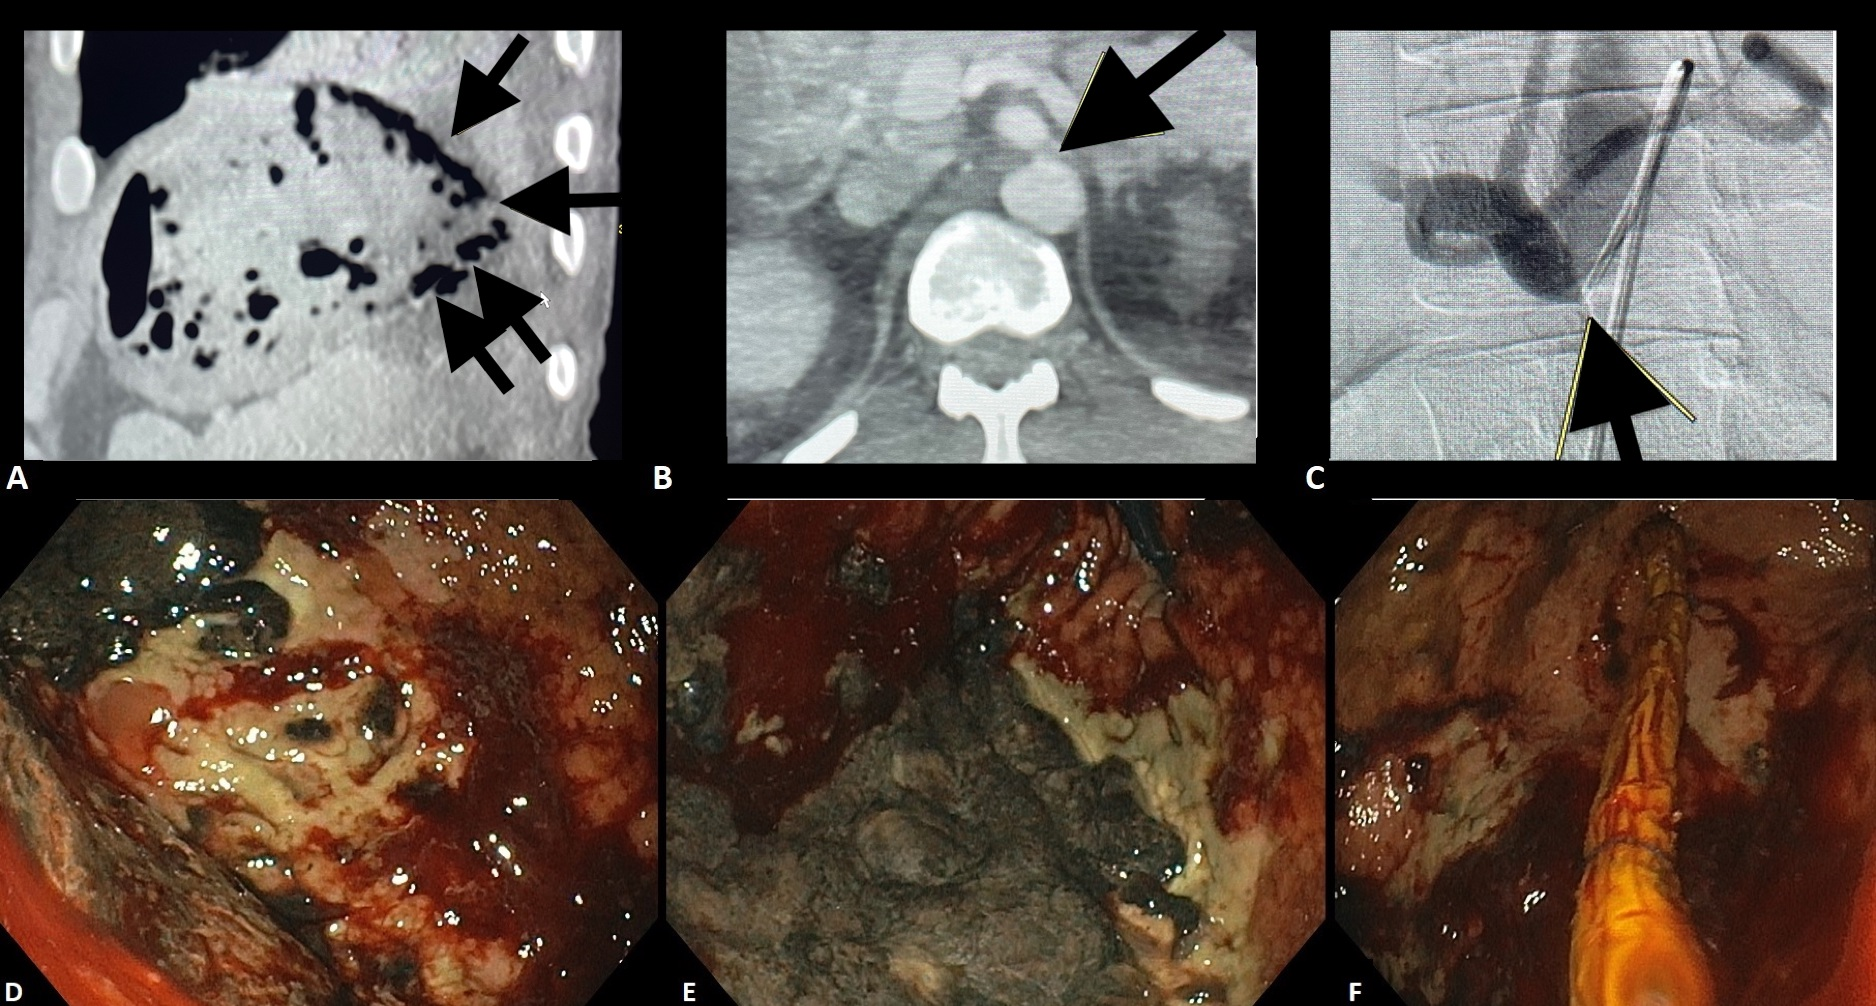

El polvo biliar se ha definido como una imagen hiperecoica flotante, sin sombra acústica posterior, observada o acentuada tras la palpación abdominal³. Se trata, por lo tanto, de la misma entidad ecográfica que, en Brasil, tradicionalmente se ha denominado “microlitiasis”, pero que no se ajusta a la definición de consenso internacional de microlitiasis y terminó siendo prácticamente ignorada por el consenso, o, en algunos casos, incluida a la fuerza bajo el término “lodo biliar”.

El polvo biliar se definió como una imagen hiperecoica flotante, sin sombra acústica posterior, observada o acentuada tras la palpación abdominal — una entidad ecográfica anteriormente denominada “microlitiasis” o “microcálculo” en nuestro medio. La introducción de este término busca conciliar los hallazgos ecográficos frecuentemente observados en la práctica diaria con las definiciones establecidas por el Consenso Internacional de 2023.